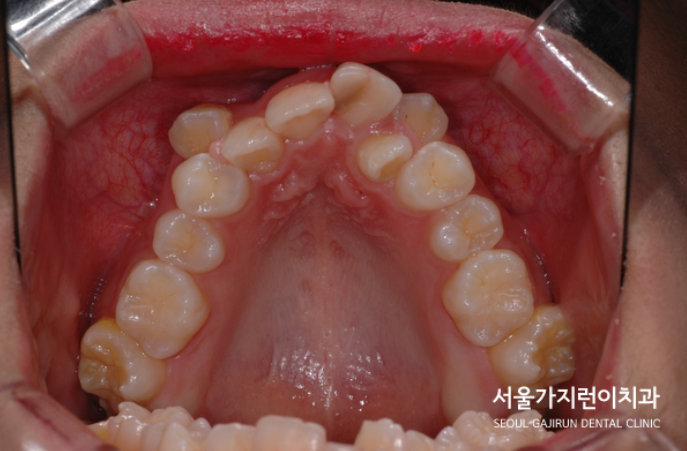

그래서 환자분의 경우 치아가 정상적인 위치에 자라지 못해 덧니로 발현된 게 아닌가 싶었는데요. 환자분의 나이가 20대 초반인것을 감안하면 덧니로 인한 외모 콤플렉스가 안타까운 상황이었습니다. 그래서 저희 서울가지런이 치과 교정과 의원에서는 덧니의 원인을 파악해 교정플랜을 수립했는데요. 환자분의 경우 턱뼈가 작거나 치아가 상대적으로 큰 경우 생기는 공간 부족으로 판단하고 공간의 확보를 위해 상악, 하악의 작은 어금니를 발치한 후 초기 단계부터 미니스크류를 식립해 앞니를 배열해나갔습니다. 사실 배열이야 가능했어도 앞니의 뻐드러진 느낌까지 잡기에는 쉽지 않았는데요. 돌출감도 해결해야 했기 때문에 LAMI 테크닉을 이용한 상악 구치 후방이동을 시행했습니다. 사진을 보면 레버암과 미니스크류를 확인할 수 있습니다.

악궁확장 장치, LAMI 테크닉은 본원의 임승민 원장님의 논문으로 발표된 바 있는데요. 입천장을 가로지르는 철사로 입실천장의 미니스크류가 상악 어금니의 뿌리를 어금니의 머리와 같은 비율로 후방 이동시킬 수 있게 해주는 것이었습니다. 이렇게 되면 상악 치열이 많은 양의 후방이동을 해도 안정성이 확보될 수 있는데요. 교정치료 후 결과를 보시겠습니다.